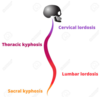

cervical spine (lordosis/kyphosis)

lordosis

thoracic spine (lordosis/kyphosis)

kyphosis

lumbar spine (lordosis/kyphosis)

lordosis

sacral spine (lordosis/kyphosis)

kyphosis

lordosis: define

normal inward CONCAVE curvature of the lumbar and cervical regions of the human spin

kyphosis: define

normal outward CONVEX curvature in the thoracic and sacral regions; means “bent backward”